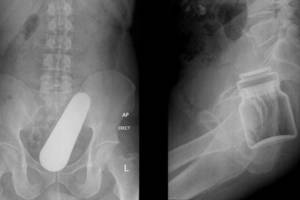

Kai Liverpulio Waltono ligoninėje buvo atliktas rentgenas, jis kartu su 50 metų žmona Tess šalia stuburo smegenų pastebėjo šuns snukį. Jie negalėjo nustoti juoktis.

Jie ginčijosi ir bandė nuspręsti, į kokią šuns veislę šis snukutis buvo panašus ir nutarė, kad jis labiausiai primena spanielį negu biglį.

„Tai buvo viena iš tų siurrealistinių akimirkų. Nuo tada mes juokaujame, kad tai „loja“. Šuns nosis yra būtent toje vietoje, kur vėžys veikia mano kūną“, – naujienų portalui „Daily Mail“ pasakojo Peteris.